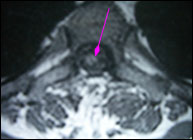

胸髓内血管网织细胞瘤(外院术后)

男性,43岁,14年前无诱因出现左下肢无力、走路不稳,渐加重并延至右下肢。9年前在外院行手术治疗,病理为“海绵状血管瘤”,术后感觉、运动功能恶化,需扶拐行走,且感觉、运动障碍日渐加重,后期伴发皮肤烫伤、便秘、小便失禁,生活质量严重下降。

术前图片:

手术在显微镜下进行,术中完整切除髓内桑椹样肿瘤,术后患者可自己翻身,部分感觉恢复,生活质量较术前明显改善。术后病理回报为海绵状血管瘤。